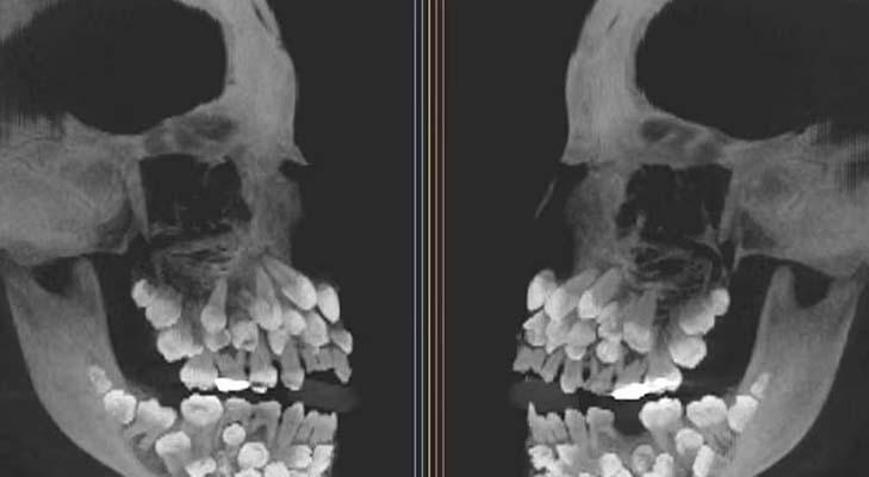

Brezilya'da yaşayan 11 yaşındaki bir kız çocuğu, sadece düşmek üzere olan bir süt dişini çektirmek için diş hekimine götürüldü. Ancak sıradan bir işlem olması beklenen bu randevu, kısa sürede tıp dünyasını bile şaşkınlığa uğratan bir olaya dönüştü.

Doktorlar, çene röntgenine baktıklarında gözlerine inanamadı. Genç kızın ağzında tam 81 diş vardı yani normalin neredeyse üç katıydı. Üstelik bu fazla dişlerin bir kısmı damakta görünürken, büyük kısmı etin içinde, henüz yüzeye çıkmamış şekilde saklanıyordu.

Peki bu kadar fazla dişe neden sahipti? Üstelik hiçbir sendrom ya da kalıtsal rahatsızlık belirtisi yoktu. Genetik testler, 9. kromozomda yapısal bir bozukluğu işaret etse de, uzmanlar hala bu durumun nedenini kesin olarak açıklayamıyor. Dişlerin boyutları ve konumları da son derece ilginçti; bazıları gelişimini tamamlamıştı, bazılarıysa minyatür şekilde, adeta çene içinde saklanmış bir "diş müzesi" gibiydi.